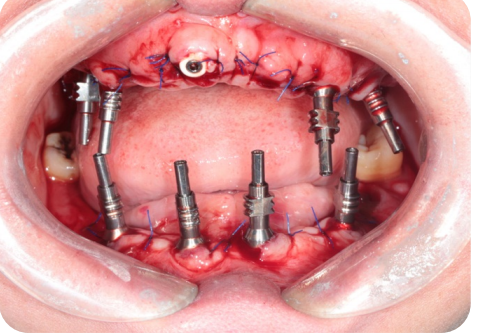

病例展示7

3合一數字化愈合基台         减少就诊次数、降低配件成本、降低戴牙时间、可以口扫、藻酸盐、硅橡胶取模方式!